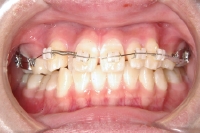

上顎の内側に装置

上顎の外側にセラミックブラケットを装着